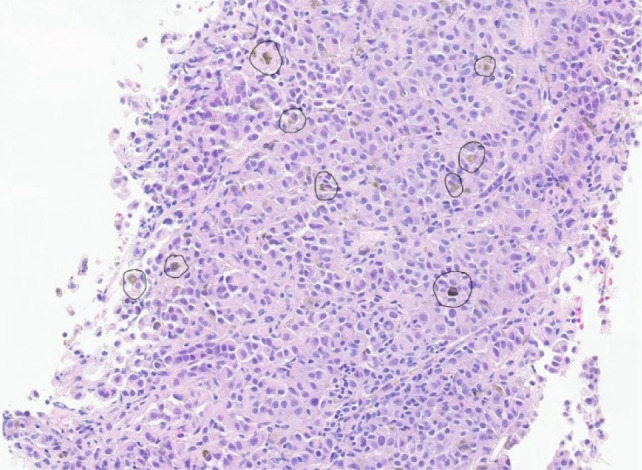

眼部黑色素瘤是黑色素瘤的一种形式,它很少提供可操作的突变来进行全身治疗,并且相对具有放射抗性。因此,手术是局部疾病的主要治疗方法,可以考虑治疗少转移性疾病。我们报告一例眼部黑色素瘤在初次诊断并接受眼内近距离放射治疗9年后复发并单发肾转移。经过多学科的讨论,患者接受了部分肾切除术,她的单发肾转移。患者在部分肾切除术后持续随访3.5年。在确定多灶性疾病后开始全身治疗之前,她再次接受了手术治疗,原因是单纯转移到乳房。鉴于黑色素瘤和其他形式的癌症治疗前景的迅速变化,我们建议对转移性侵犯靶器官的患者进行跨学科管理。

Ocular melanoma is a form of melanoma that rarely offers actionable mutations for treatment with systemic therapy and is relatively radioresistant. As such, surgery is the mainstay of treatment for localized disease and can be considered for oligometastatic disease. We present a case of ocular melanoma that recurred with a solitary renal metastasis 9 years after initial diagnosis and treatment with intraocular brachytherapy. After multidisciplinary discussion, the patient underwent a partial nephrectomy for her solitary renal metastasis. The patient continued in follow-up 3.5 years after partial nephrectomy. She was treated again surgically for a solitary metastasis to the breast before initiation of systemic therapy once multifocal disease was identified. We suggest interdisciplinary management of patients with metastatic involvement of target organs, given the rapidly changing treatment landscape for melanoma and other forms of cancer.